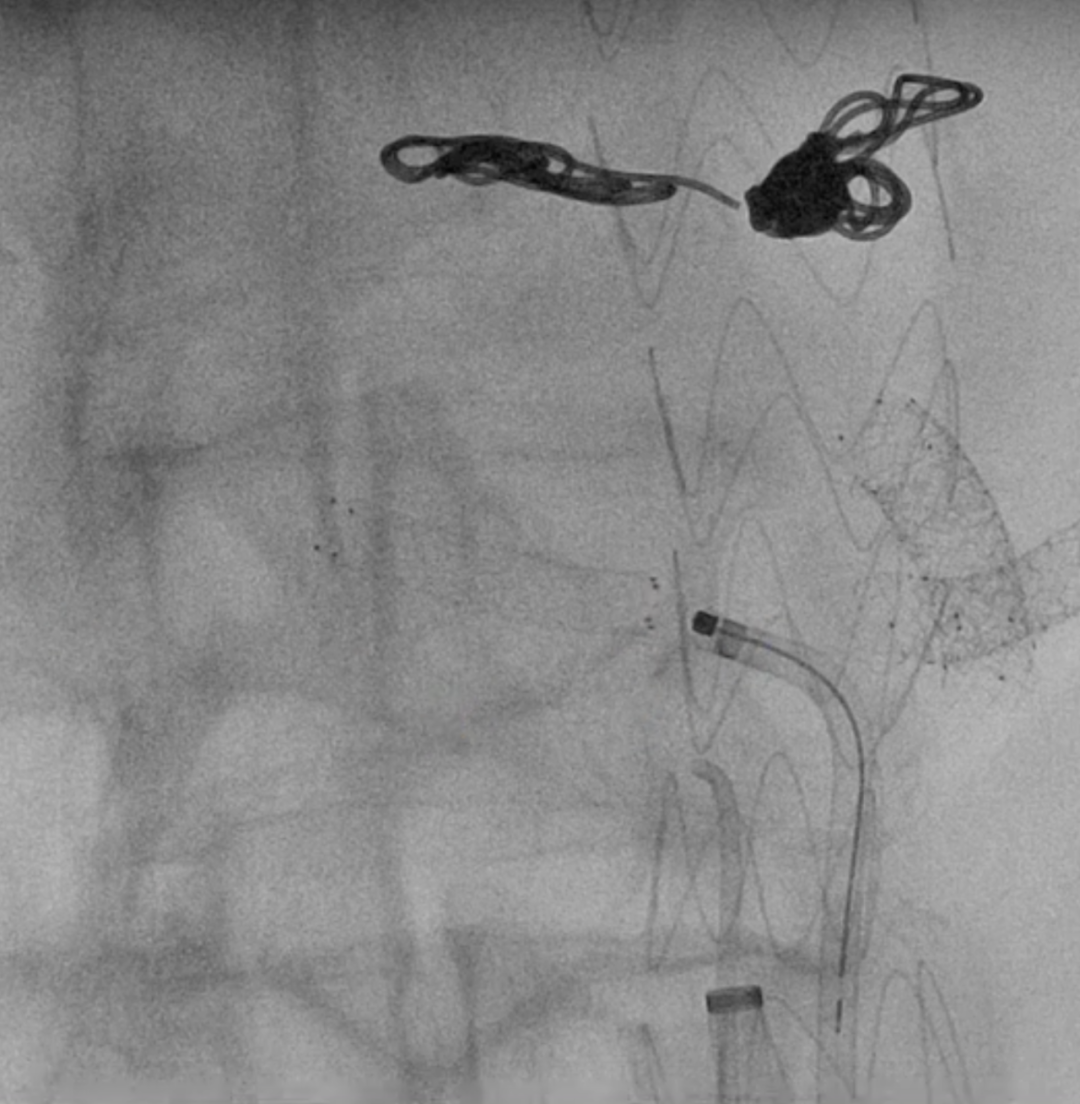

在胃十二指肠动脉分叉前栓塞腹腔干动脉。

在植入主动脉支架后,首先开通SMA,配合可调弯导管调整激光导管角度,多角度视图下确保对准。发射激光(60-60mJ/mm2),激光穿透主体支架覆膜后立即推进导丝。

确认导丝进入靶血管后移除激光导管,依次使用4mm快交球囊、5mm切割球囊进行扩张开窗,交换入35系统导丝,在预植入的支架内引入VBX球扩覆膜支架,远端超过预植入支架远端,近端伸入主动脉3-5毫米,扩张球囊使VBX释放。

再次扩张VBX支架近端使其锚定于主动脉支架上。

造影确认开窗支架的通畅性。

在其他目标动脉内重复以上操作。

在激光开窗前多角度确认。